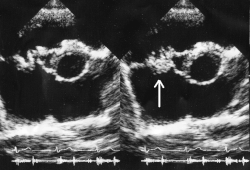

A infecção frequentemente produz vegetações, que são estruturas compostas de plaquetas, fibrina e microrganismos infecciosos. O aspecto da vegetação à ecocardiografia é de uma massa de material ecogênico, aderida a uma superfície endocárdica, geralmente anormal (valvas alteradas, locais de shunts, etc), e que apresenta uma mobilidade diferente da mobilidade da superfície à qual está aderida. Localiza-se geralmente na câmara para onde se dirige a regurgitação (face atrial na valva mitral e ventricular na valva aórtica) e tende a crescer nos folhetos das próteses biológicas e no anel das próteses mecânicas.[5] Nas valvas, ela pode se limitar às cúspides, mas pode invadir o anel ou as estruturas adjacentes, causando distúrbios de ritmo, comunicações entre as cavidades ou mesmo grandes abscessos. Ela pode acometer a valva mitral, a aórtica, a tricúspide ou a pulmonar e, com freqüência, lesando mais de uma. O acometimento pode ser por bactérias gram+, gram – ou por fungos.[6] Atualmente, alterações valvares degenerativas e próteses, e não mais a doença reumática, representam as causas mais comuns de endocardite em países desenvolvidos.[5]

Vegetação na válvula tricúspide vista em um ecocardiograma

5. Ecocardiograma com evidências de endocardite (há 3 possíveis achados ecocardiográficos: massa intracardíaca oscilante ecogênica em sítio de lesão endocárdica, abscesso perivalvar e nova deiscência em valva prostética)